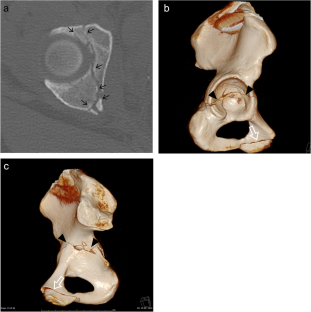

Fig. 2